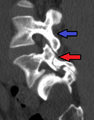

Spondylolisthesis L5/S1

Spondylolisthesis L5/S1 Spondylolisthesis L5/S1

Spondylolisthesis L5/S1 Spondylolisthesis L5/S1. Blue arrow normal pars interarticularis. Red arrow is a break in pars interarticularis

Spondylolisthesis L5/S1. Blue arrow normal pars interarticularis. Red arrow is a break in pars interarticularis Spondylolisthesis L5/S1

Spondylolisthesis L5/S1